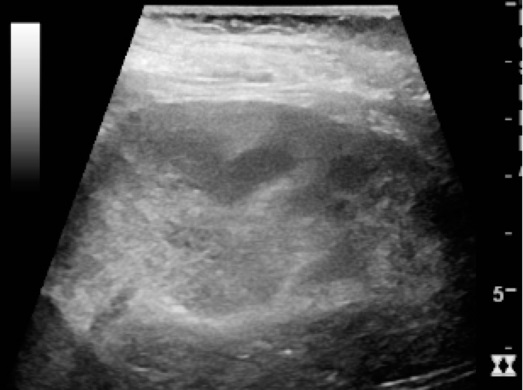

Pyelonephritis is kidney infection.

Pyelonephritis is usually brought on by ascending infection.

Vesicoureteral reflux is a risk factor of pyelonephritis.

Pyelonephritis presents with:

- Leukocytosis

- Fever

- Flank discomfort

- White blood cell casts

Chronic Pyelonephritis

Chronic pyelonephritis results in cortical scarring with blunted calyces.